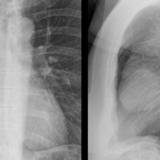

Case 1b

Thymoma

Date: 03/17/2004

Views: 4922